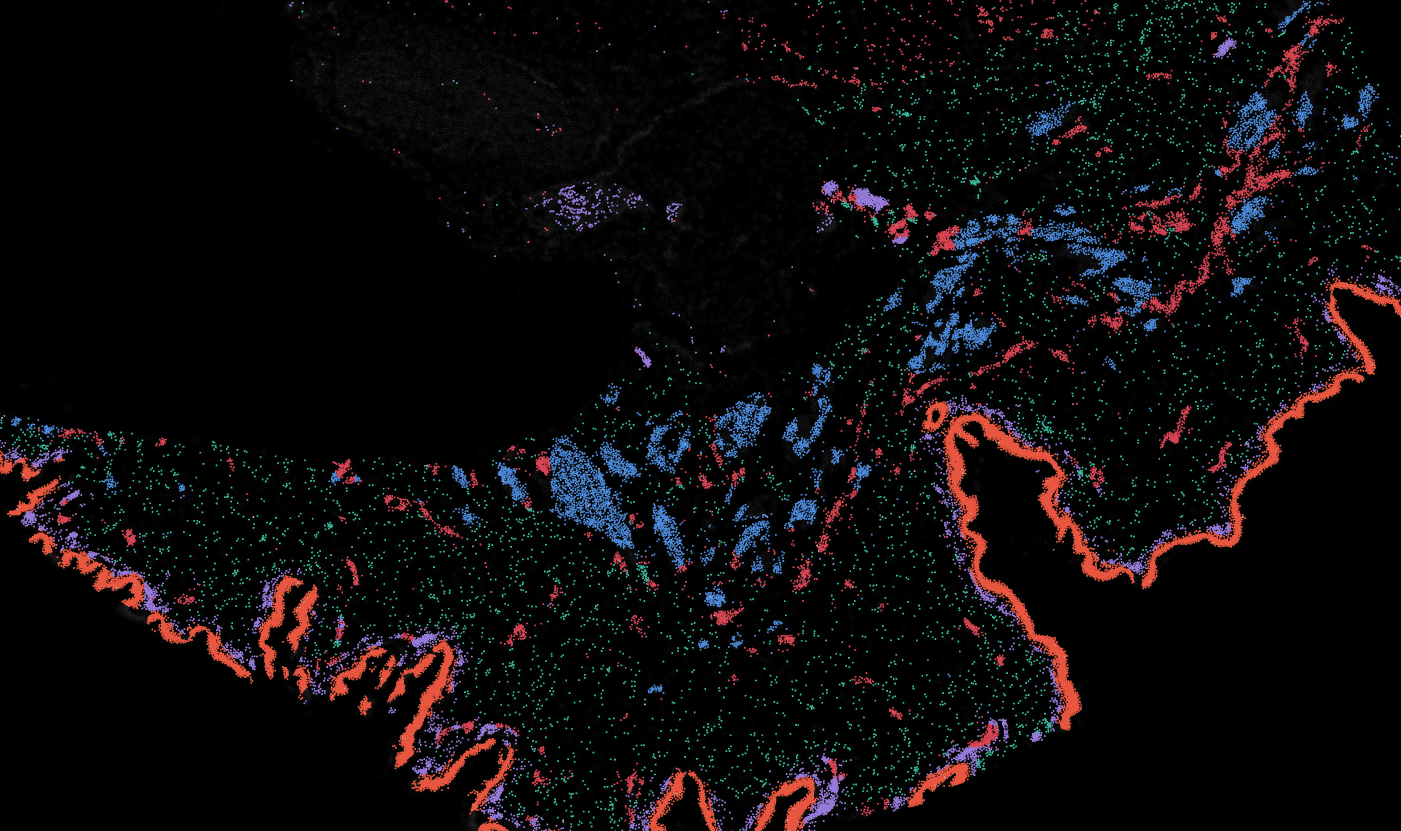

Applicability across different spatial resolutions

The segmentation module is designed to help researchers explore tissue architecture at multiple levels of detail, depending on their scientific question. Users can begin by dividing the tissue into major anatomical structures to gain a broad overview of the spatial landscape. From there, they can zoom into a specific region of interest and further segment it into sub-tissue compartments, enabling more refined analysis of microenvironments and localized biological processes.

Streamline multi-omics data collaboration

OmnibusX brings research teams even closer together. Pathologists can now seamlessly annotate tissue images, providing critical insights that drive deeper biological analysis for every team member.